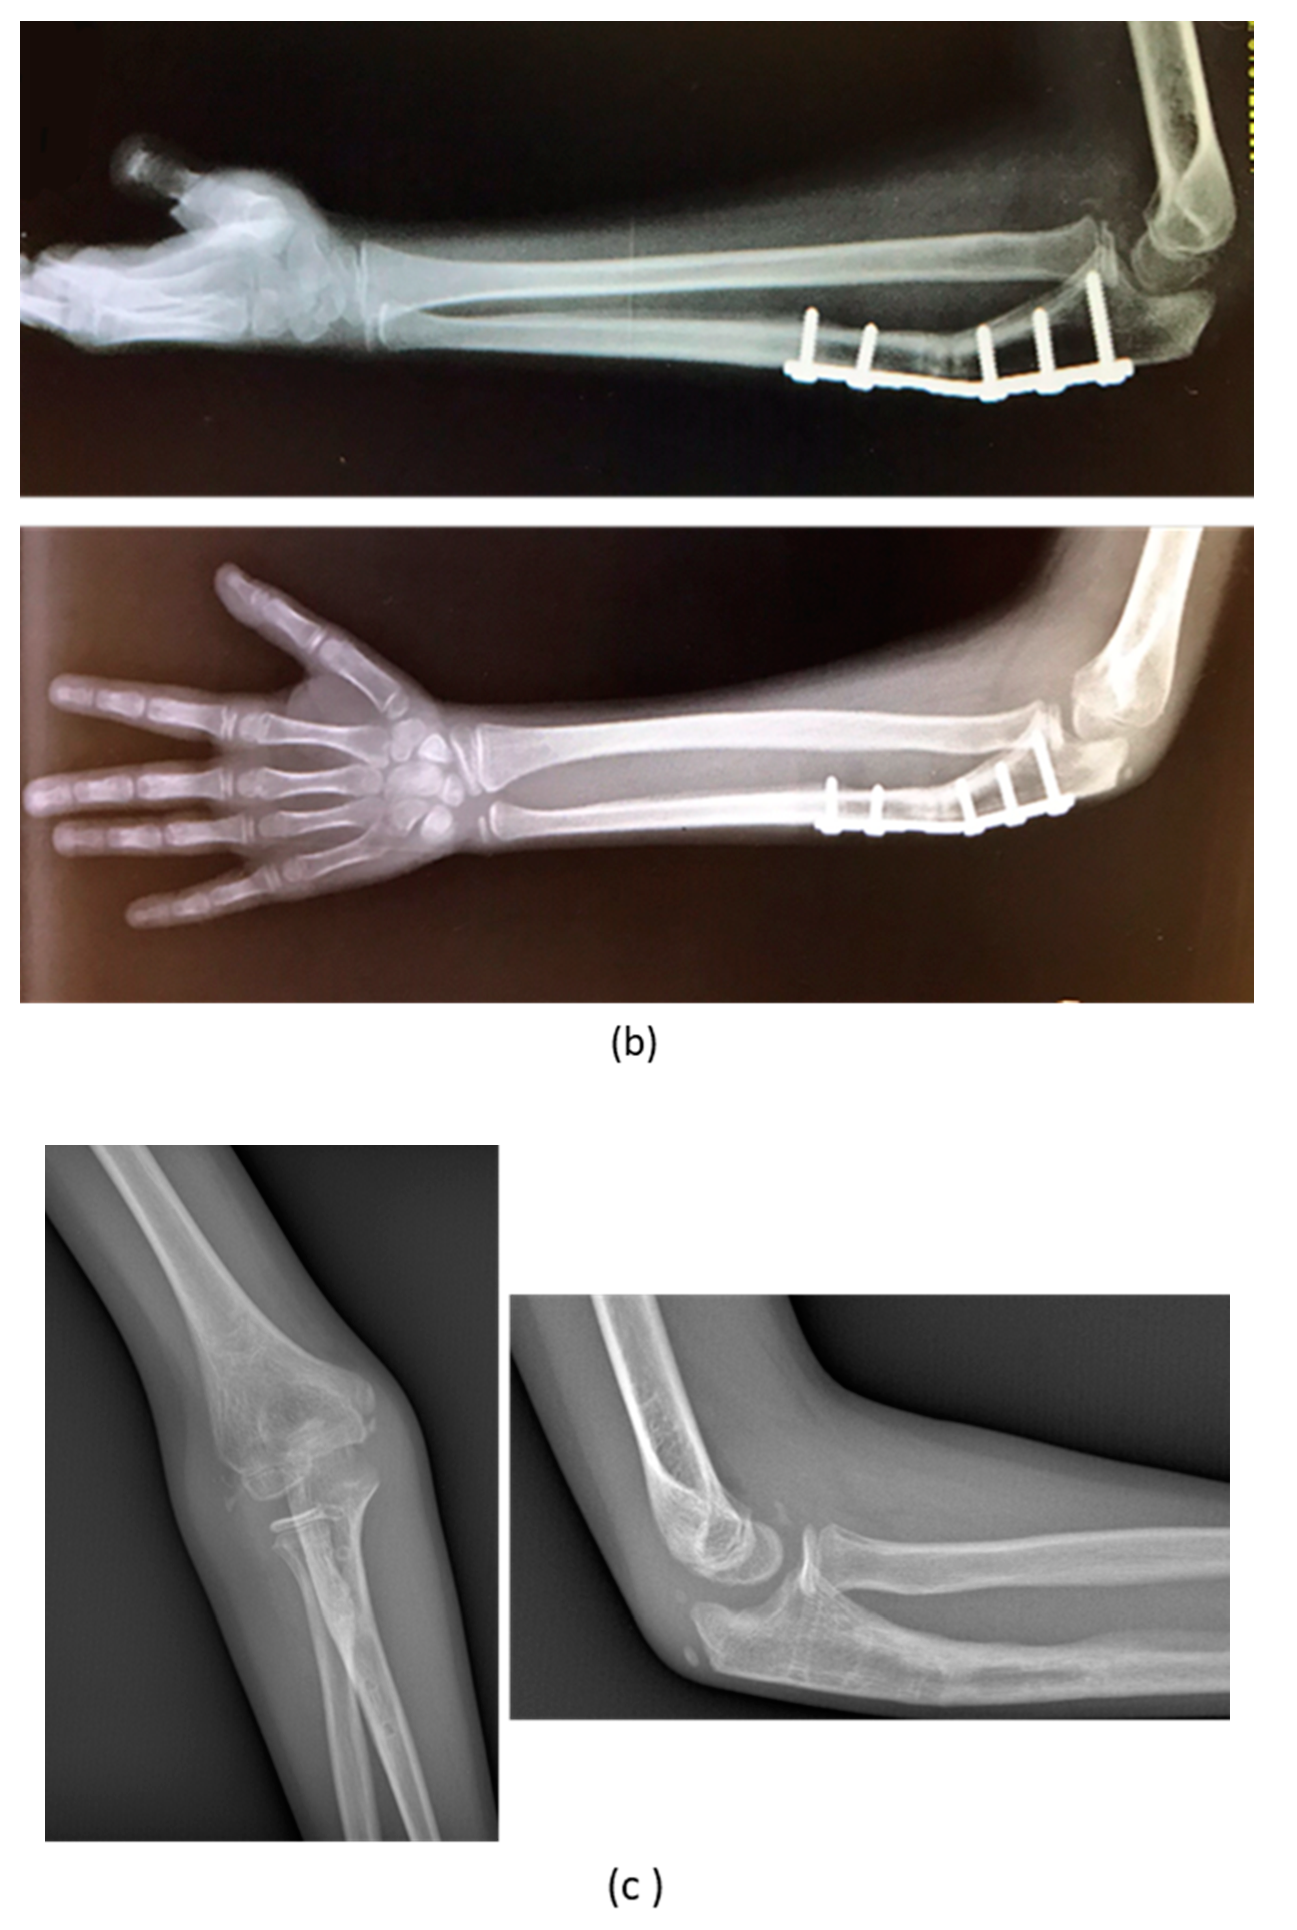

| 3 | M, 15 | Post-traumatic forearm malunion deformity | Post-traumatic | Bifocal osteotomy stabilized with 1/3 tubular plate | None | Corrected |